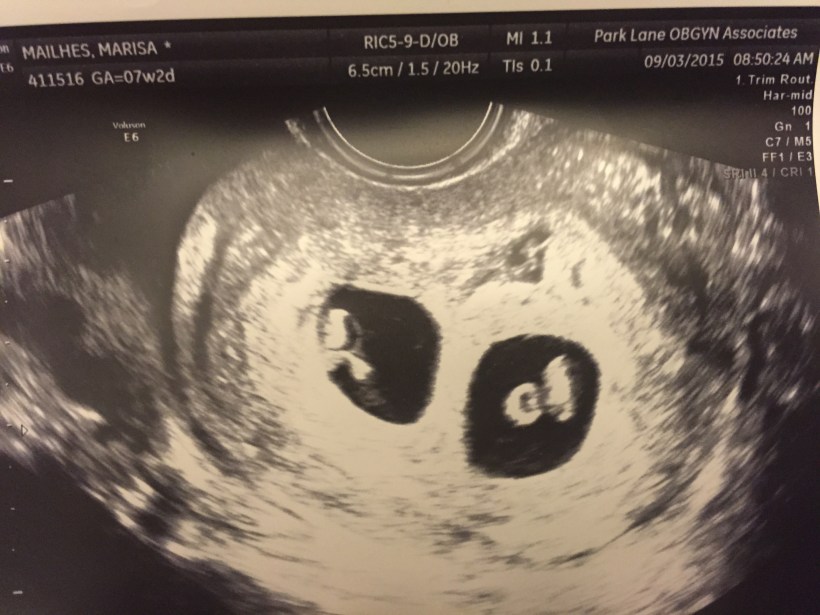

We walk into the sonogram room and the tech says “lets see how many babies are in there” and laughs. I barely hear her because I am so nervous and even when I realize what she said I brush it off because its not even a thought in my head. Colbie is parked in her stroller right in front of the monitor that shows everything and Trey is sitting next to me. I have my eyes covered because I just cannot handle the thought of bad news. The tech BARELY starts the sonogram and says “Oh! There ARE two in there!” I immediately uncover my eyes and see the unmistakable picture of twins. (I didn’t actually know what twins would look like that early on, but when you see it on the sonogram you just KNOW its twins). Colbie giggles and looks up at me and then I look at Trey. Biggest eyes you’ve ever seen! He can’t speak and I just start laughing. I am so relieved that there is nothing wrong, so relieved there actually is a baby in there (omg there’s 2 in there!) and so unbelievably in shock that I can’t do a single thing, but laugh.

– The twins were what is known as di/di twins (Dichorionic/Diamniotic)- which means they each have their own amniotic sac and their own placenta. This is the lowest risk version of twins.

– Di/Di twins are most commonly fraternal, but there was no way to tell if ours were fraternal or identical until we had them and either had a DNA test or could just tell by looking at them